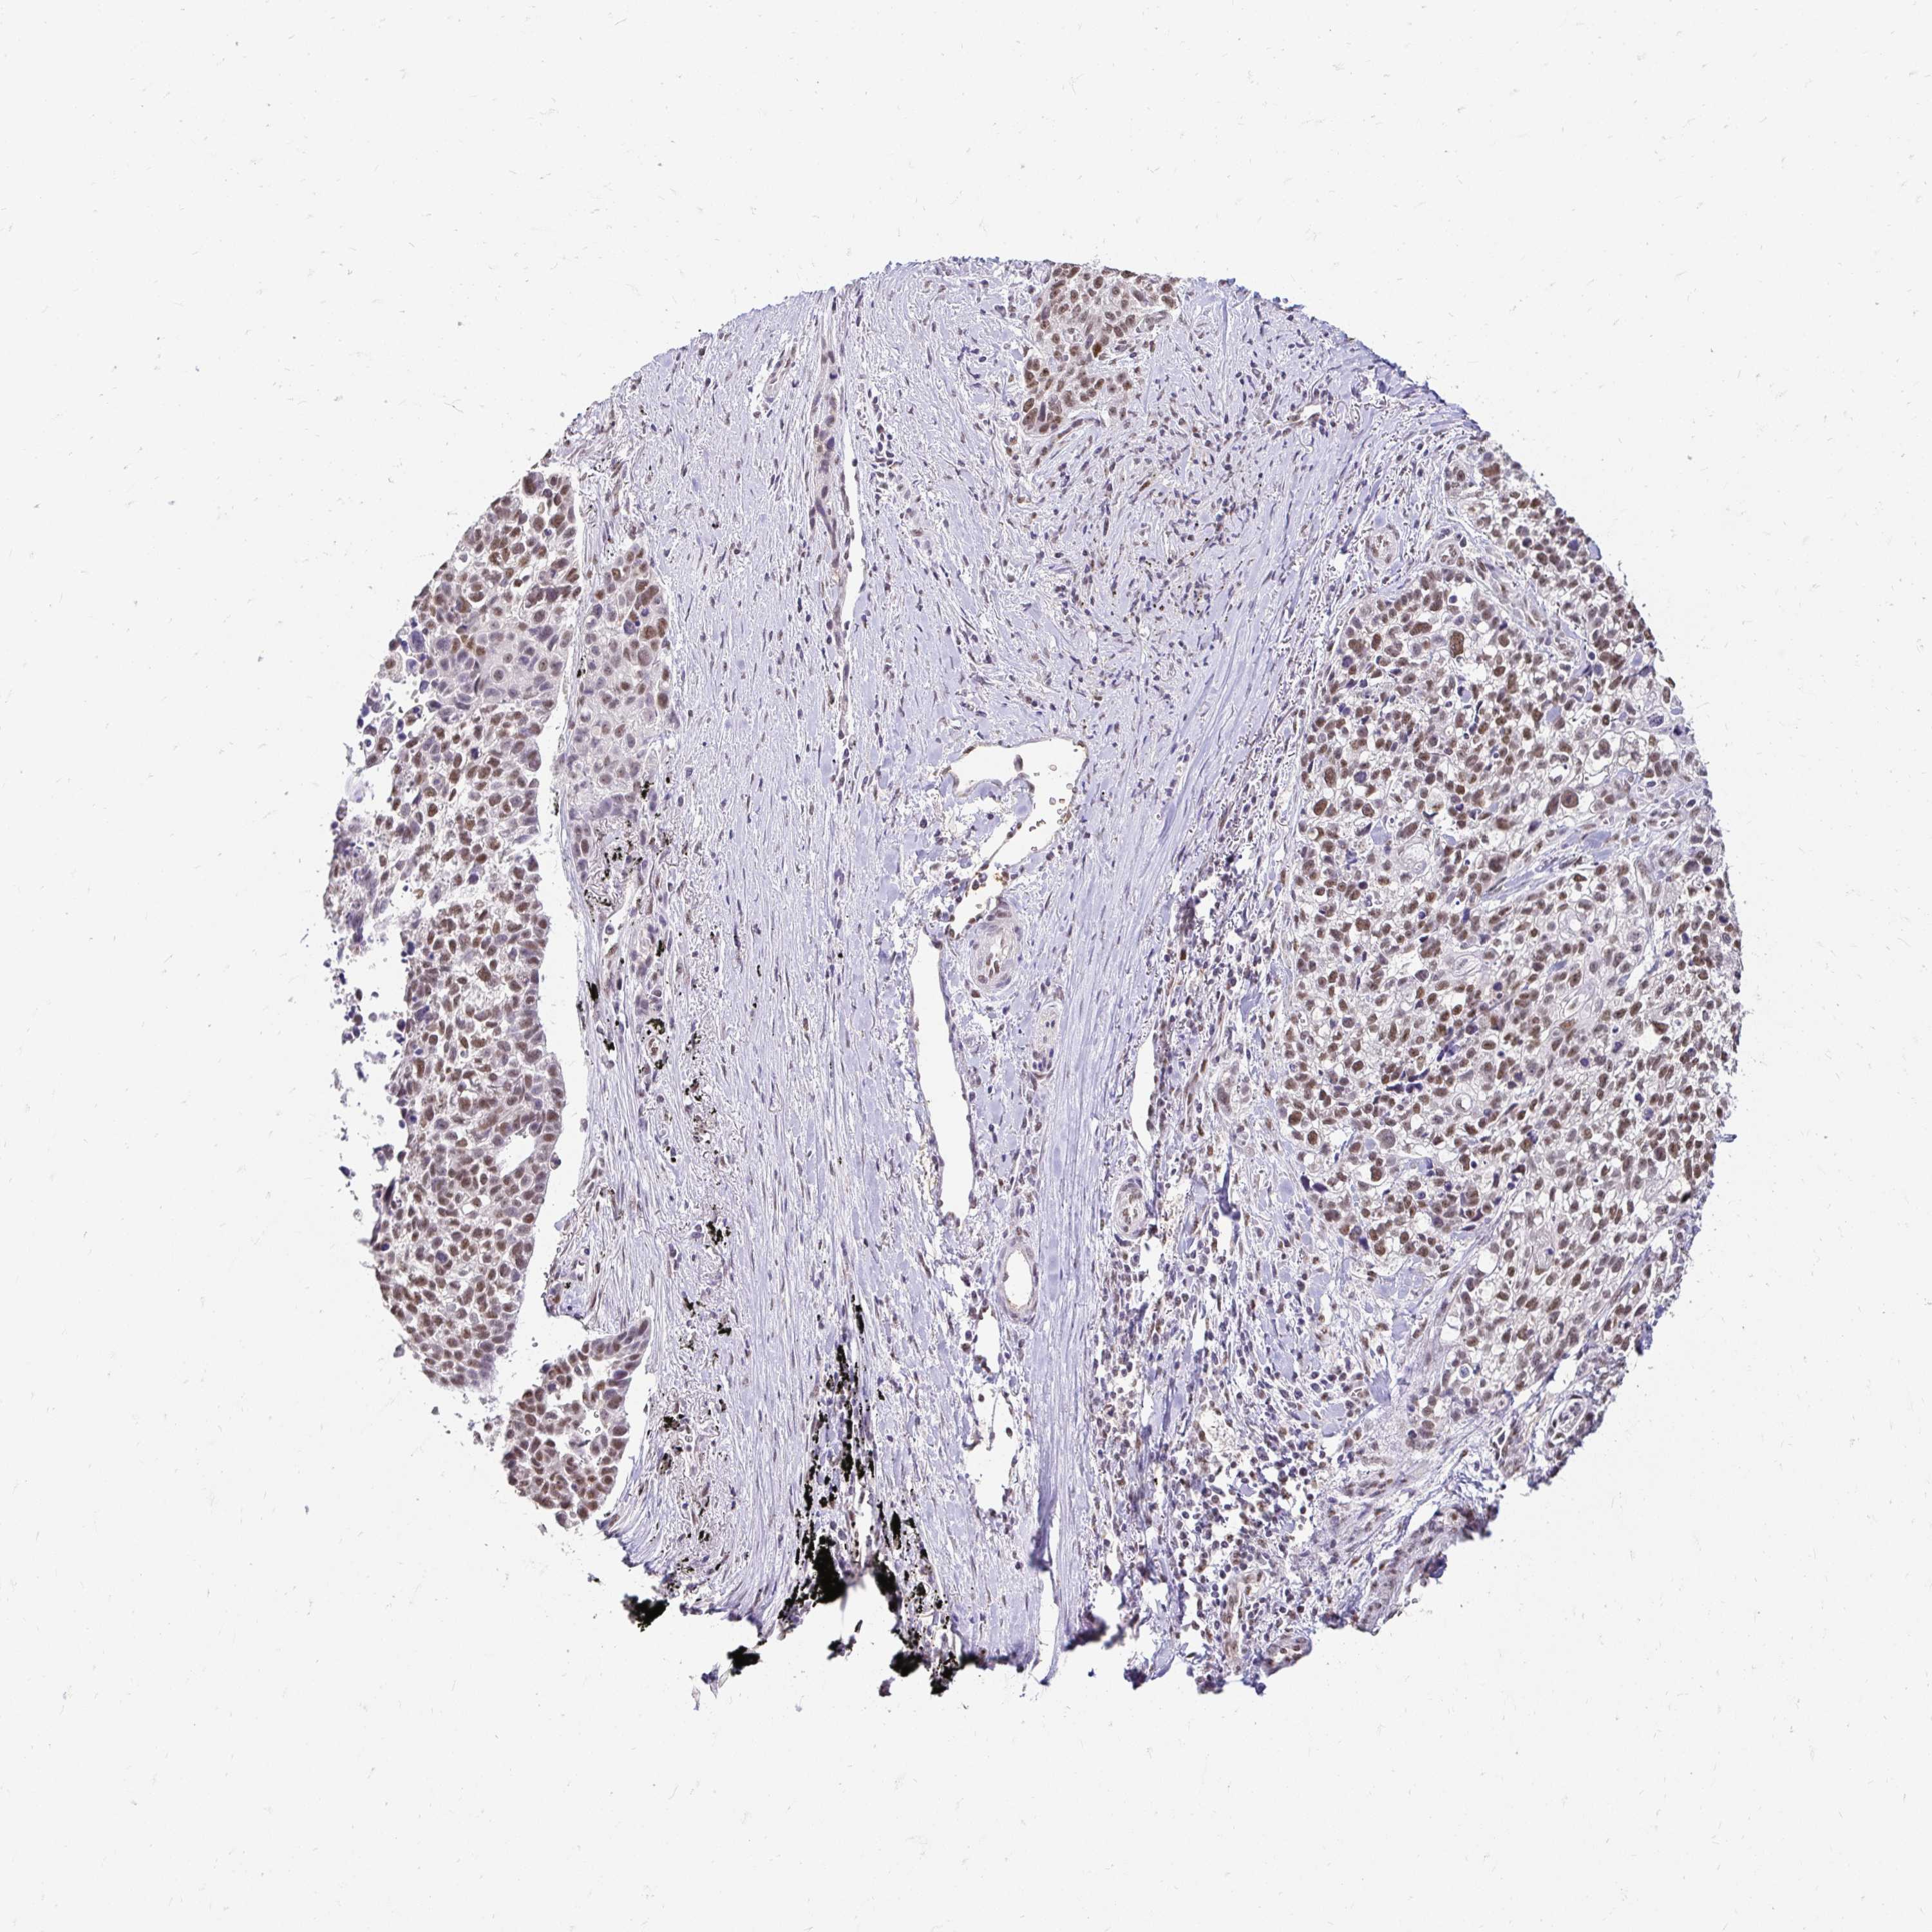

CANCER LUNG CANCER Show tissue menu

LUAD TCGA LUAD VALIDATION LUSC TCGA LUSC VALIDATION PROTEIN LUAD CPTAC PROTEIN LUSC CPTAC PROTEIN EXPRESSION